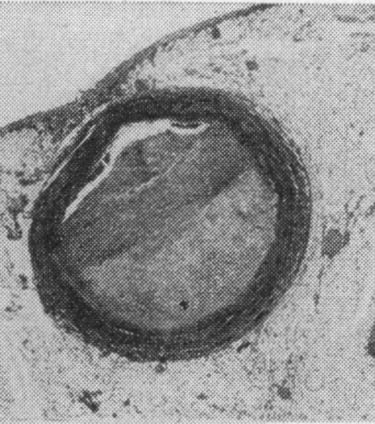

The shocking insights from people die from war show 77% of their hearts had “gross evidence”—meaning visible-to-the-eye evidence—of coronary atherosclerosis, hardening of their arteries. Some of them had vessels that were clogged off 90% or more. their average age? 22 years old

cross section through anterior descending artery of a 22-year-old white man killed by penetrating shell fragment wound of the head.